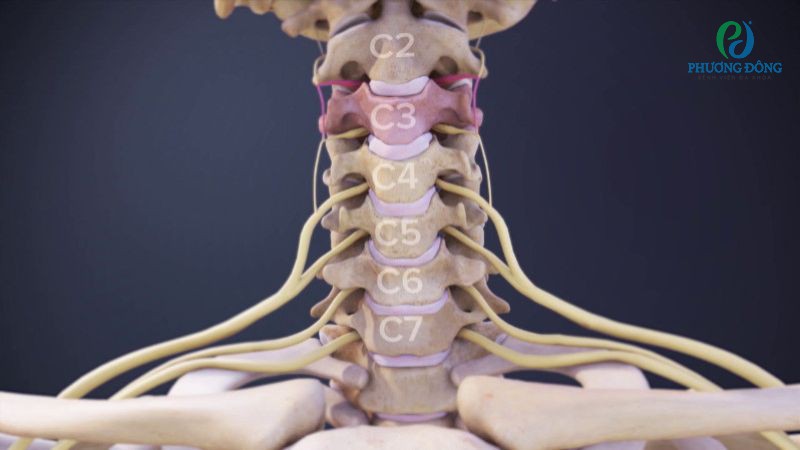

Gai đốt sống cổ

Gai đốt sống cổ là thuật ngữ chỉ tình trạng đốt sống cổ bị thoái hóa, chèn ép lên dây thần kinh. Bệnh thường diễn tiến âm thầm với các triệu chứng không quá đặc trưng, người bệnh dễ chủ quan điều trị dẫn đến những biến chứng nguy hiểm.

Các gai xương hình thành tập trung chèn ép lên các vị trí như tủy cổ, rễ thần kinh vùng cổ, động mạch sống. Từ đó gây nên một số vấn đề điển hình như hội chứng cổ - vai, hội chứng chèn ép tủy cổ, hội chứng động mạch đốt sống - thân mềm và hội chứng cổ - vai - cánh tay.

Hình ảnh gai cột sống cổ chèn ép lên dây thần kinh